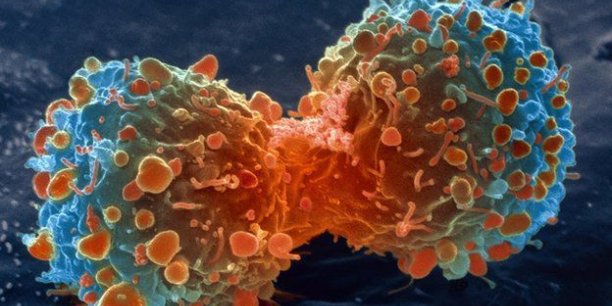

Pourquoi les jeunes scientifiques peuvent détenir la clé d’une cure contre le cancer . Les scientifiques en début de carrière et en milieu de carrière sont confrontés à des obstacles plus difficiles que leurs collègues plus expérimentés, ce qui peut décourager les jeunes esprits créatifs à la recherche d’une chance de trouver des remède pour […]